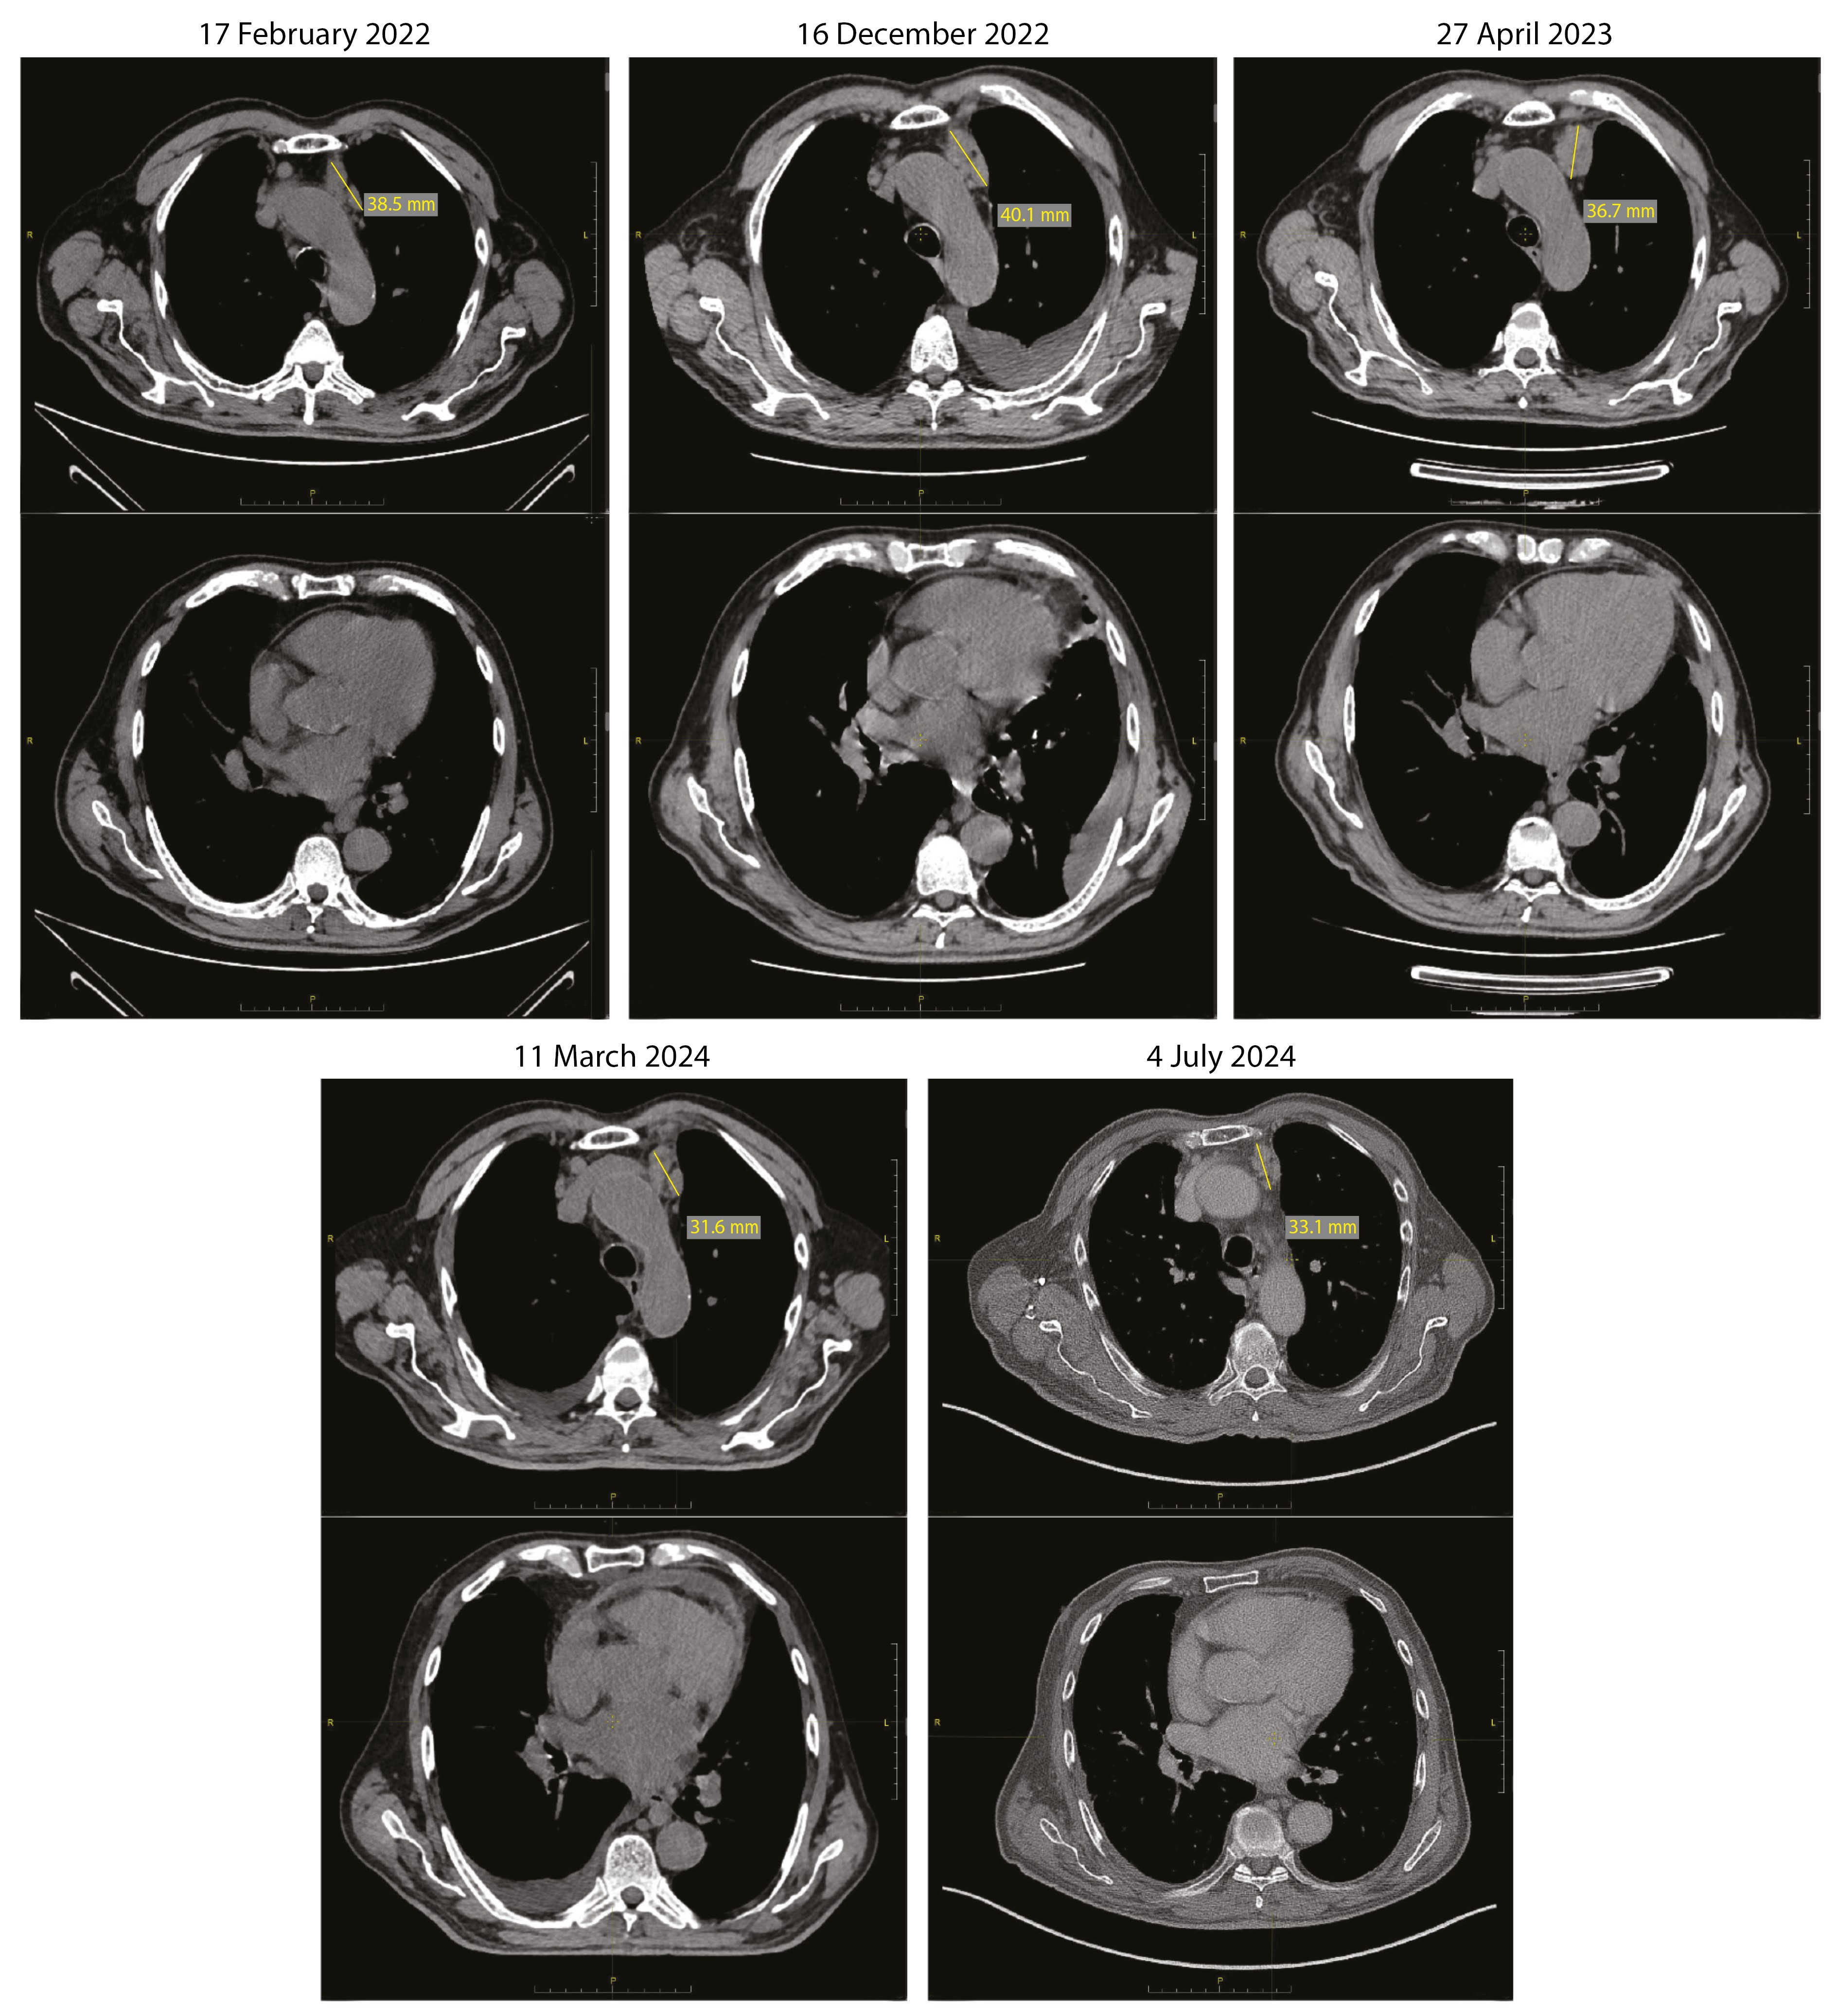

Повторно проведена Эхо-КГ (21.03.2024, рис. 3). По сравнению с предыдущим исследованием ФВ – 46%. Отмечается «дрожание» межжелудочковой перегородки. Отсутствует скользящее движение перикарда в области верхушки и боковой стенки ЛЖ. Количество жидкости в полости перикарда небольшое, без значимой динамики в сравнении с предыдущим исследованием: за задней стенкой ЛЖ – до 8 мм, над ПЖ – до 6 мм, диастолического коллапса ПЖ нет. При доплеровском исследовании – выраженное изменение скорости кровотока от фаз дыхания: на вдохе скорость трансмитрального кровотока снижается более чем на 25%, транстрикуспидальный кровоток повышается более чем на 25%. Выраженная дилатация НПВ – диаметр 34 мм, на вдохе не коллабирует. Диастолическая функция миокарда нарушена: E/A – 0,8, Elat – 10 см/с (N > 10 см/с), Emed – 8,7 см/с (N > 7 см/с), E'lat/E'med – 1,16 (N > 1,2, annulus reversus). Выявленные изменения свидетельствовали о том, что ведущим механизмом одышки и отеков у пациента была констрикция – ограничение подвижности миокарда выпотом и ригидным перикардом [14].

Рис. 3. Эхокардиограмма пациента: А – парастернальная позиция, длинная ось ЛЖ, систола; Б – парастернальная позиция, длинная ось ЛЖ, диастола; В – доплеровское исследование транстрикуспидального кровотока; Г – доплеровское исследование трансмитрального кровотока. Ао – аорта, ЛЖ – левый желудочек, ЛП – левое предсердие, ПЖ – правый желудочек. Белый треугольник указывает прослойку жидкости в перикарде